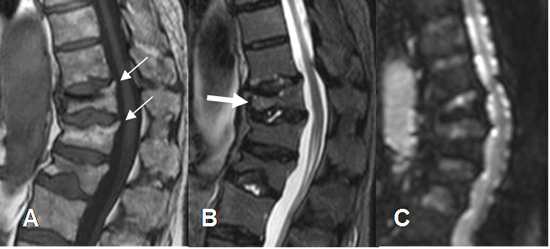

Fig 218. Fractura benigna.

A: Rx lateral, B: TAC reconstrucción sagital, C: RM sagital en T1 y D: RM sagital en STIR. Fractura vertebral hipointensa en T1 e hiperintensa en STIR, por evolución aguda. Sus bordes anterior y posterior son angulados, lo que sugiere origen benigno. (Flechas). Existe fragmento retropulsado.